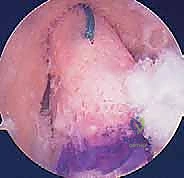

الخطوة الأولى: الفحص بالمنظار الجراحي 4K

يستخدم الدكتور